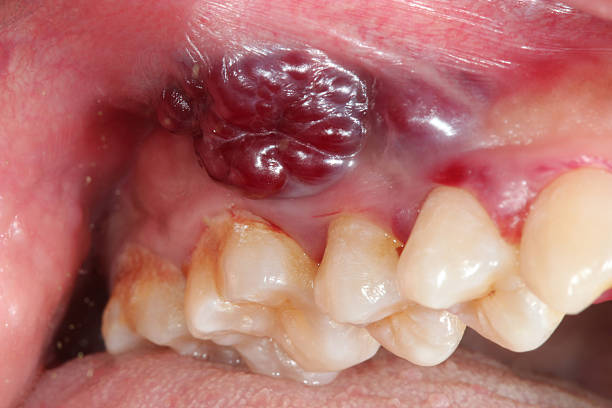

The retromolar trigone is a small triangular area located behind the last molar on the lower jaw. Despite its size, its proximity to vital structures like the jawbone, muscles, lymph nodes, and throat makes any cancer in this region potentially dangerous and quick to spread.

RMT cancer is a subtype of oral cancer and is often classified under head and neck cancers. It typically manifests as squamous cell carcinoma, though other variants are possible.

Non-healing ulcers or lesions in the region behind the last molar

Lump or swelling behind the molars or on the jaw